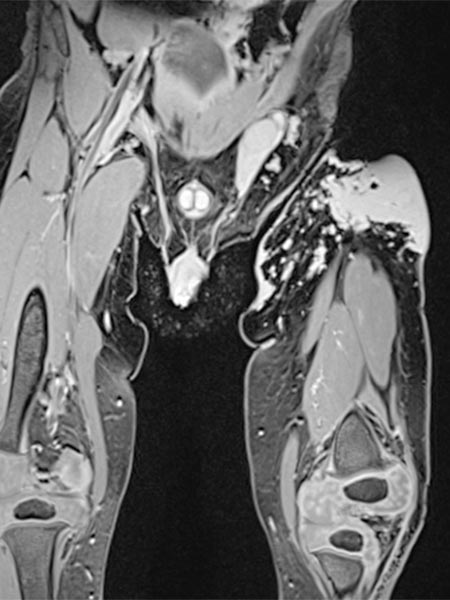

Die koronare, T2-gewichtete, fettgesättigte MRT zeigt den Tumor in der linken Leiste homogen stark hyperintens (13. Lebensmonat) und klar solide. Nebenbefundlich die durchnässte Windel, ebenfalls mit hoher Signalintensität.

Gleiche MRT-Sequenz, koronare Schichtführung. Der Tumor liegt nicht nur epifaszial, sondern zeigt auch eine geringe Ausdehnung nach subfaszial unter die Fascia lata in die Glutealmuskulatur. Damit klar infiltratives Verhalten.

Auch in der axialen Schichtführung der MRT (T2-gewichtet, fettgesättigt) ist die Infiltration der Muskulatur durch die Raumforderung gut dargestellt. Auch Hämangiome können als vaskuläre Tumoren eine solche Infiltration aufweisen, ohne dass sie maligne sein müssen.

In der nativen koronaren T1-gewichteten MRT ist der Tumor isointens zur Muskulatur ohne enthaltene Fettgewebsanteile. Er ist somit in dieser Sequenz kaum von der Muskulatur abgrenzbar.

Die axiale T2-Wichtung ohne Fettsättigung zeigt den Tumor homogen nur gering hyperintens. Er ist zwar hyperintenser als Muskulatur, aber insgesamt deutlich weniger hyperintens als das umgebende subkutane Fettgewebe.

Koronare, T1-gewichtete, fettgesättigte MRT nach Kontrastmittelgabe. Der Tumor zeigt ein homogenes, starkes Enhancement. Daneben zwei zentrale Flow-voids als Zeichen der starken arteriellen Perfusion.